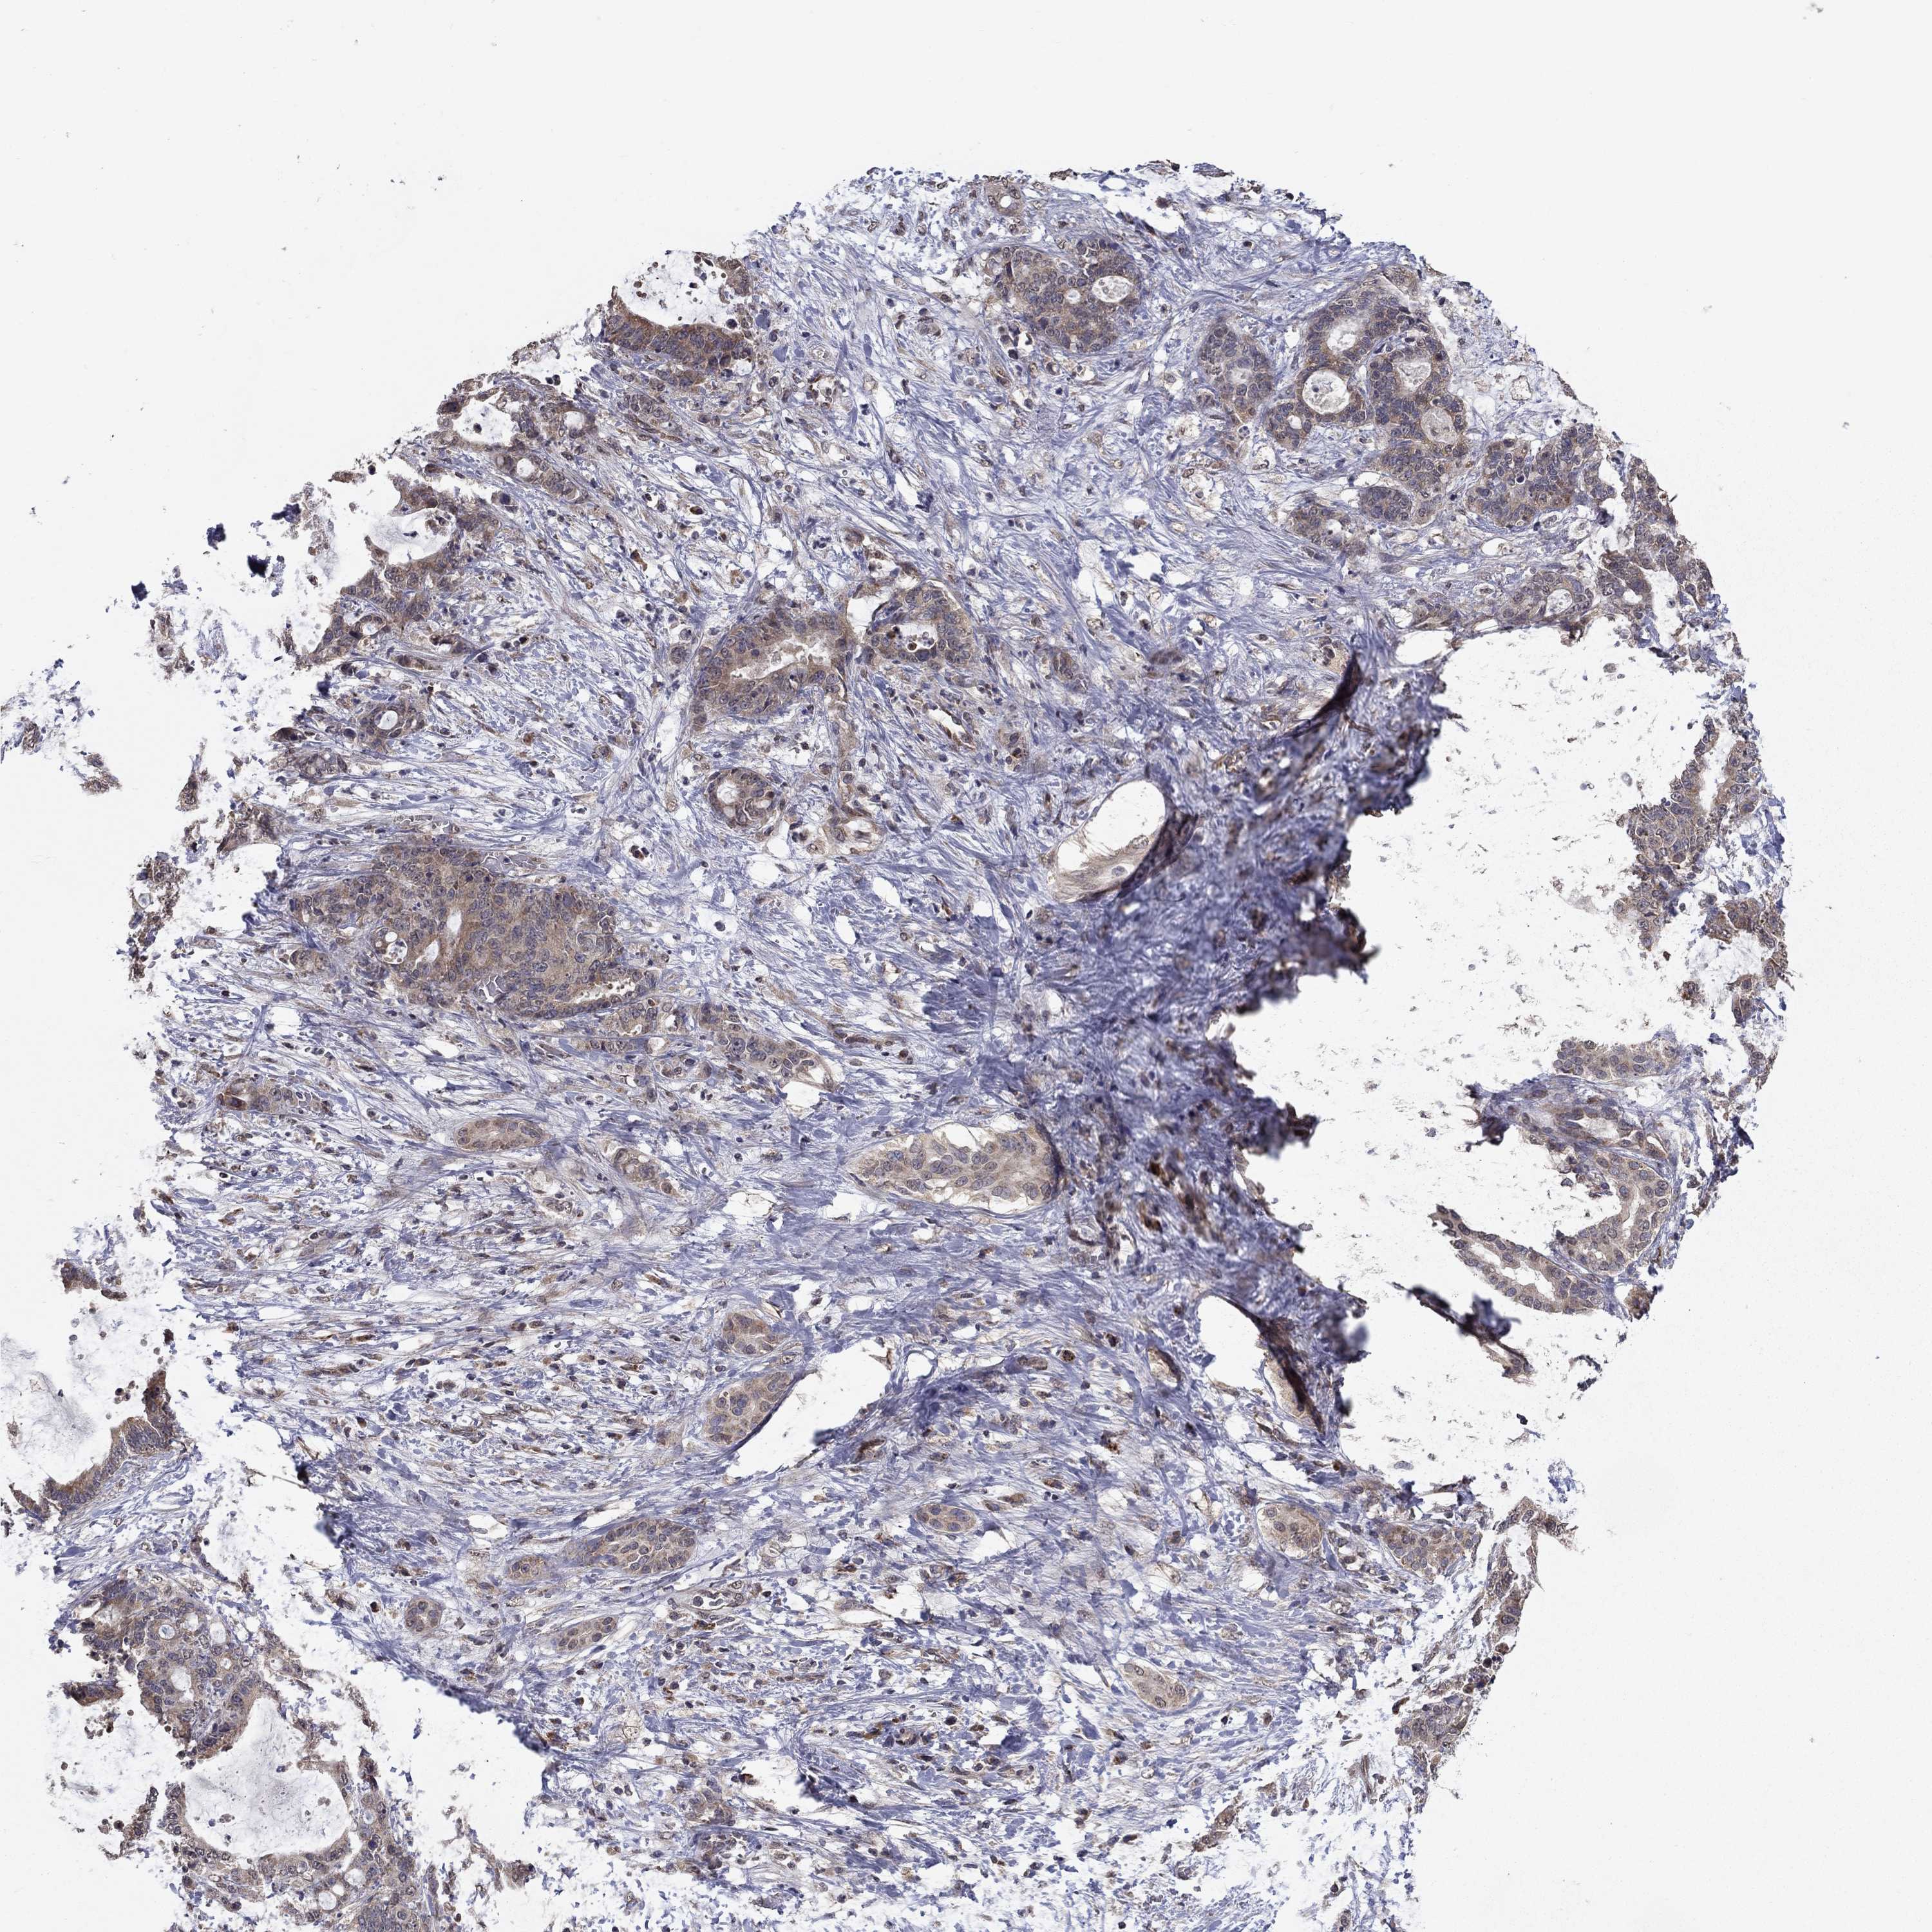

LIVER CANCER - Protein expressioni

A mouse-over function shows sample information and annotation data. Click on an image to view it in a full screen mode. Samples can be filtered based on level of antibody staining by selecting one or several of the following categories: high, medium, low and not detected. The assay and annotation is described here.

Note that samples used for immunohistochemistry by the Human Protein Atlas do not correspond to samples in the TCGA dataset.

Antibody stainingi

Antibody staining in the annotated cell types in the current human tissue is reported as not detected, low, medium, or high, based on conventional immunohistochemistry profiling in selected tissues. This score is based on the combination of the staining intensity and fraction of stained cells.

Each image is clickable and will lead to virtual microscopy that enables deeper exploration of all samples and also displays staining intensity scores, fraction scores and subcellular localization as well as patient and tissue information for each sample.

Antibody HPA006584

Antibody HPA061679

Staining

High

Medium

Low

Not detected

Intensity

Strong

Moderate

Weak

Negative

Quantity

>75%

75%-25%

<25%

None

Location

Nuclear

Cytoplasmic/membranous

Cytoplasmic/membranous,nuclear

Cholangiocarcinoma

Carcinoma, Hepatocellular, NOS